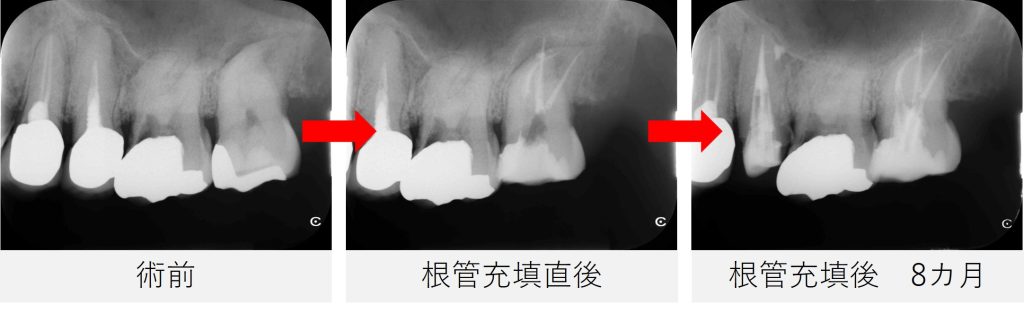

- 根管充填を行い、仮封しました。

レントゲン撮影で、根管充填の状態が良好であることを確認しました。

根管充填後は、画像と症状の両面から経過を確認していきました。

根管充填後から8カ月

- 痛みはなく、鼻の症状も認められませんでした。

- レントゲンおよびCT撮影を行い、根尖部の黒い影が縮小し、骨の回復傾向が確認されました。

- 炎症の改善が見られたため、最終補綴(被せ物の作製)へ移行する予定としました。